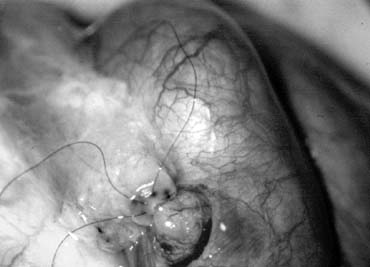

This method, also known as the triangulation technique,43 has gained increasing popularity among microsurgeons over the conventional end-to-end and end-to-side vasoepididymostomy.4,44,45,46 When the level of epididymal obstruction is clearly demarcated by the presence of markedly dilated tubules proximally and collapsed tubules distally, the site at which the anastomosis should be performed is readily apparent (Figs. 19 and 20). The vas deferens is drawn through an opening in the tunica vaginalis and secured in proximity to the potential anastomotic site in the epididymis with two to four interrupted sutures of 6-0 polypropylene placed through the vasal adventitia and the epididymal tunica (Fig. 21). Six microdots are placed on the cut surface of the vas in an identical fashion to that described for vaso-vasostomy (Fig. 22). Three 10-0 double-armed nylon sutures are placed in the epididymal tubule in a triangular fashion (Fig. 23). The needles are not pulled through but left in situ, creating a triangle of needles. A generous opening is made in the epididymal tubule in the center of the triangle created by the three needles. The three needles are then pulled through (Fig. 24). A glass slide is touched to the fluid exuding from the opening in the epididymal tubule and mixed with human tubal fluid media, covered with a cover slip and examined by the surgeon using the separate bench microscope under 400-power magnification. If sperm are present (whether motile or not) the decision is made to proceed with the anastomosis. Sperm are aspirated into micropipettes first (Fig. 25) and expressed into human tubal fluid media and sent for cryopreservation if motility is observed. After abundant sperm have been aspirated into micropipettes and cryopreserved, the six needles are passed inside out the vas deferens exiting through the six previously placed microdots in the order indicated (Fig. 26). Each pair of sutures is then sequentially tied. Tying of these sutures intussuscepts the epididymal tubule into the vas lumen (Fig. 27). This creates a water-tight closure. In addition, the flow of epididymal fluid from the epididymal tubule into the vas deferens tends to plaster the edges of the epididymal tubule against the mucosal walls of the vas deferens, further helping create a leakproof closure. The second layer of the anastomosis is completed using interrupted 9-0 nylon sutures to secure the epididymal tunica to the vasal sheath (Fig. 28).

Fig. 19. Inspection of the epididymis for dilated tubules (arrow) seen beneath the epididymal tunica.

Fig. 20. Dissection exposing dilated loops of epididymal tubule (arrow).